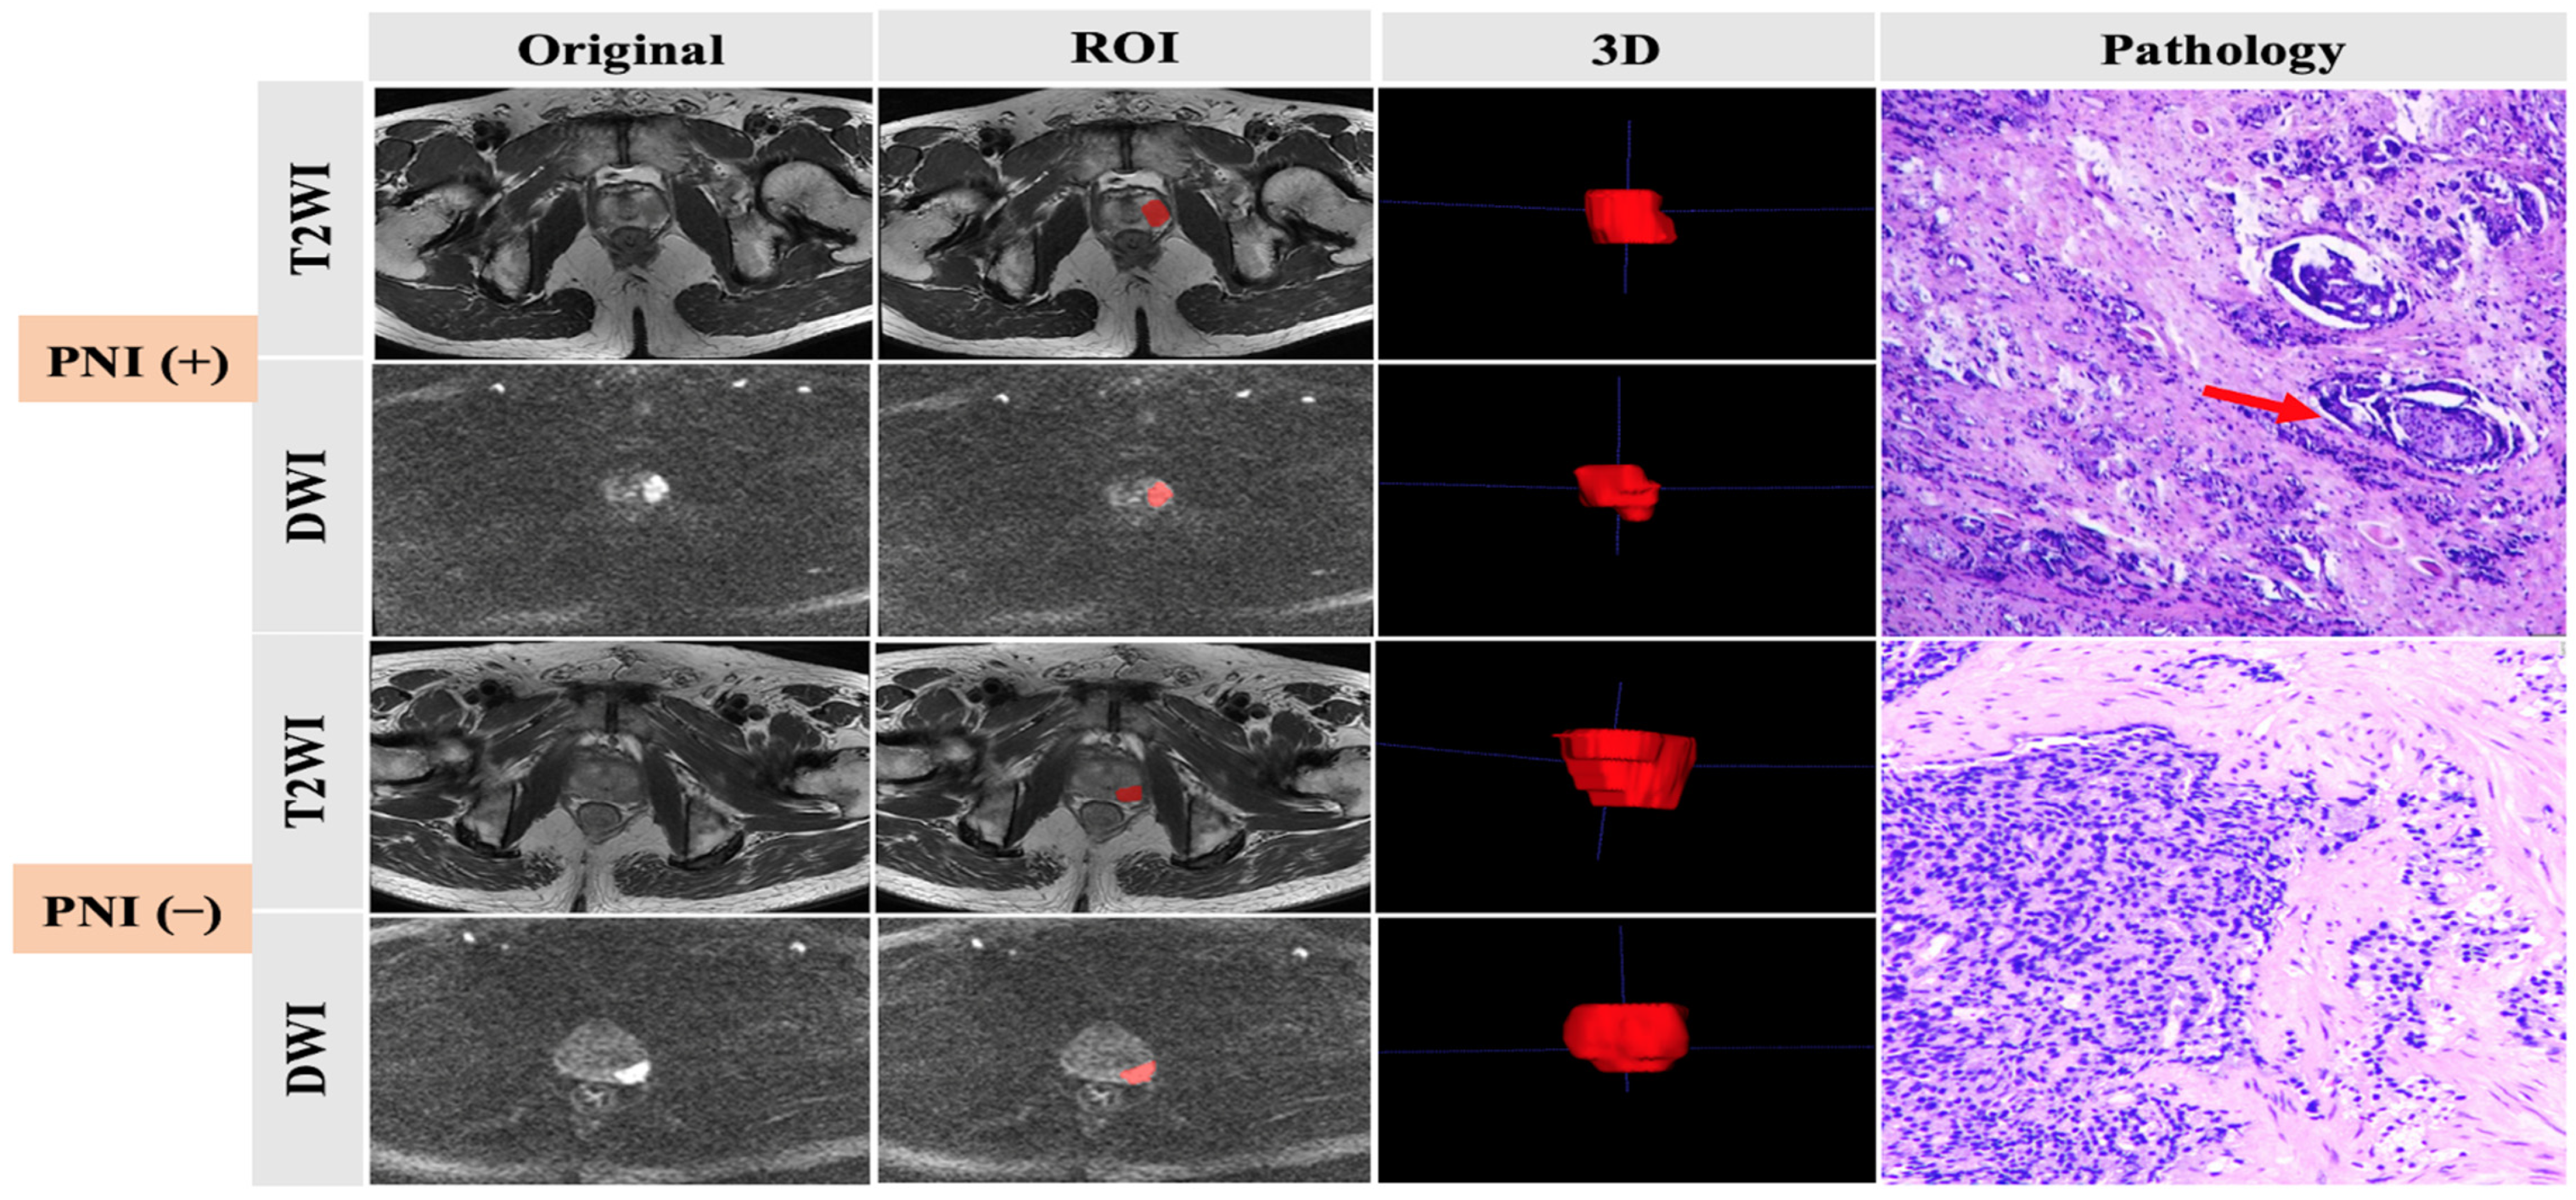

All patients underwent transrectal ultrasound-guided 12-core systematic prostate biopsy or RP after prostate MRI examination. The specimen pathological diagnosis was made by two pathologists with more than three years of experience in diagnosis of prostate diseases. The GS was updated according to the 2014 International Society of Urological Pathology criteria. PNI was diagnosed when PCa infiltration was identified in any layer of the nerve sheath or tumor invasion involved at least one-third of the nerve circumference. Pathologic information was collected, and, according to the outcomes, all patients were divided into two groups: one group had positive prostate cancer cell PNI and the other group had negative prostate cancer cell PNI (Figure 1).

Figure 1.

Preoperative MRI images, ROI delineation, and pathological comparison of prostate cancer with and without PNI, as indicated by the arrow.

2.4. Tumor Segmentation

All MR images were manually delineated by two independent readers with more than 5 years’ experience in reading prostate MR images. ITK-SNAP software was used to process T2WI and high-b-value (b = 1500) DWI images. Tumors were targeted as the regions of interest (ROIs), defined as hypointense signal areas compared with the normal prostate area on T2WI and a higher signal intensity than that of the normal prostate area on DWI. For consistency between ROIs in both T2WI and DWI images, all depicted ROIs were strictly delineated with the same criteria and visually validated by the same expert. The ROIs were manually delineated layer-by-layer along the lesion boundary, obtaining three-dimensional data (Figure 1).